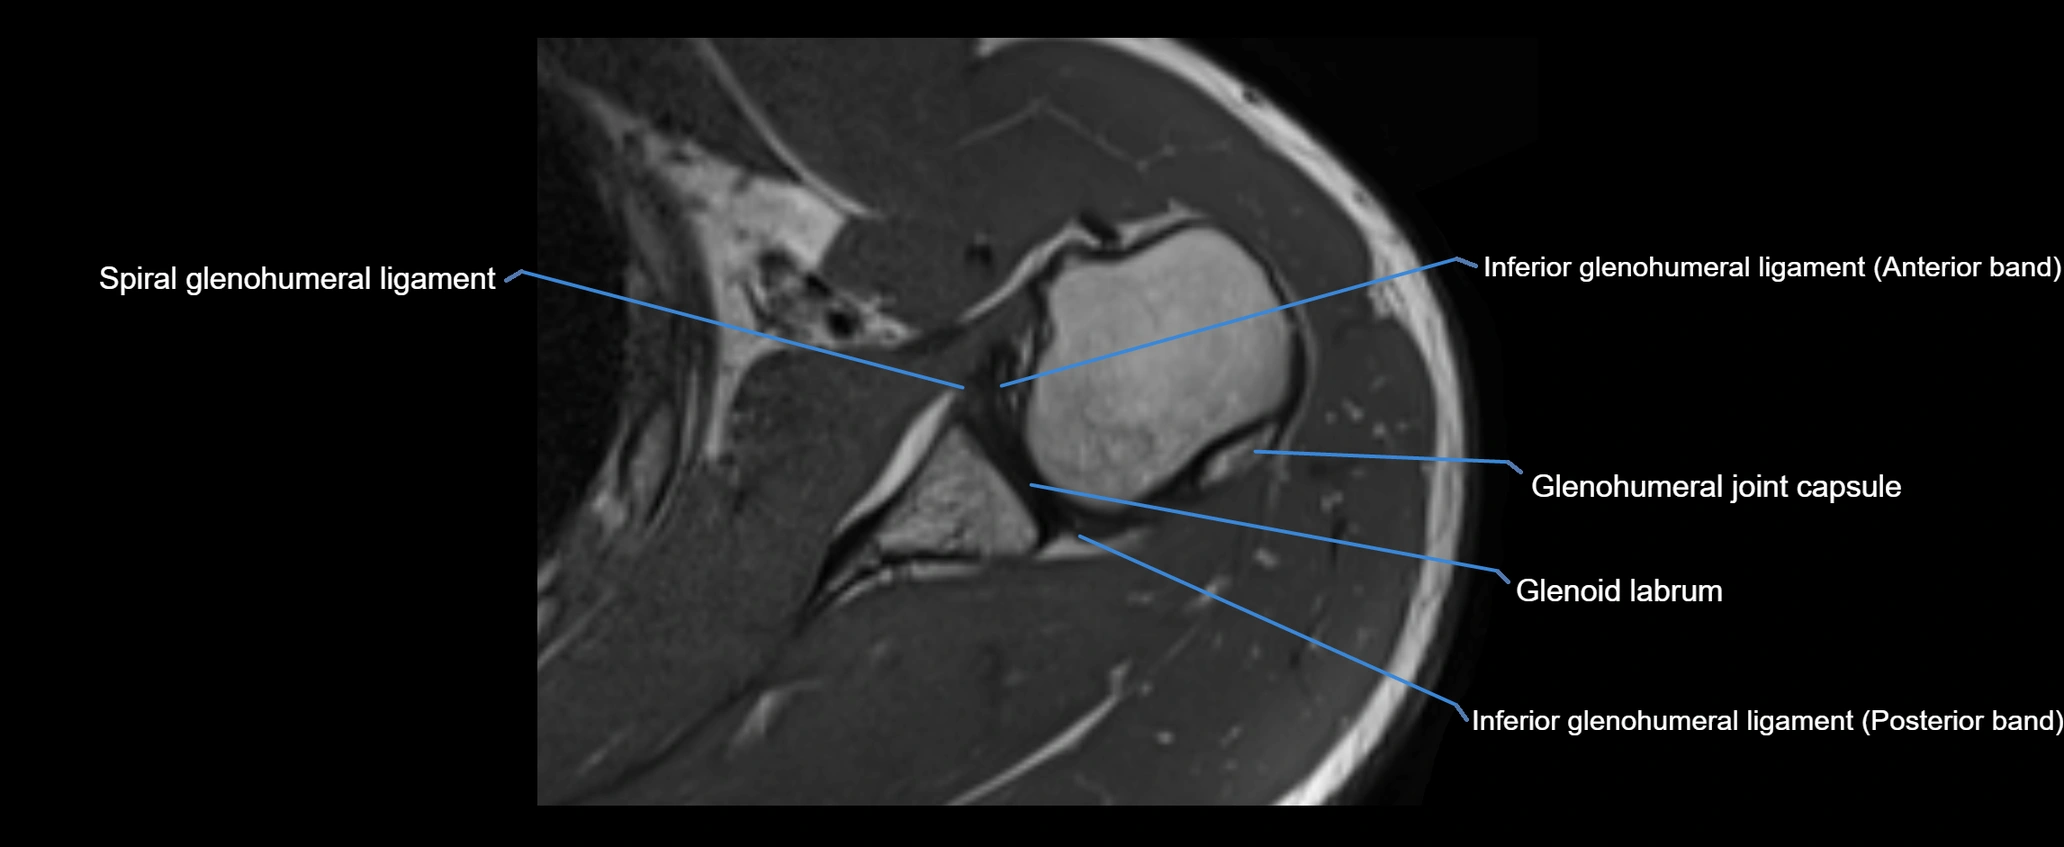

MRI images

image